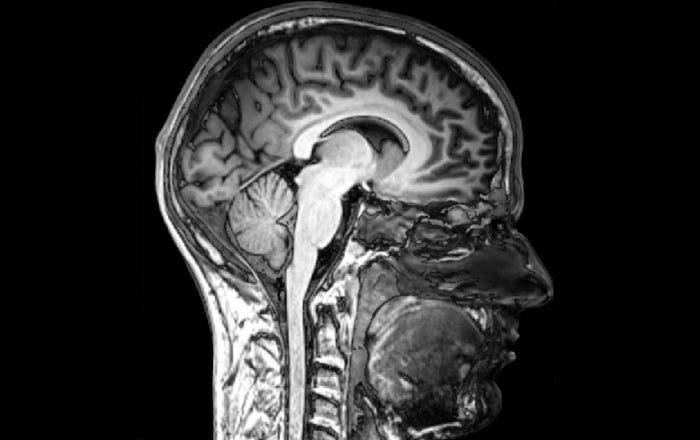

Primary psychopaths are born with the tendencies to develop into the individuals who can do real harm — both psychologically and physically. These are the people who have the warrior genes and particular brain patterns visible in PET and fMRI scans, specific to the disorder. If they also suffered physical or emotional trauma in childhood, they’re highly likely to be a real threat to family and society at large. As noted in the definition of psychopathy in the PPI (or Psychopathic Personality Inventory), many of them exhibit “fearless dominance”. This type of trait makes them charismatic and self-confident. These people are glib fast-talkers, easily able to manipulate others. They’re immune to stress and lack any true emotional empathy or warmth. Fearless dominance is a trait we admire in our leaders — our politicians and corporate CEOs. We perceive these people as being strong and capable. They’re comfortable making the difficult decisions the rest of us go out of our way to avoid. Dr. Fallon pointed to Teddy Roosevelt, FDR, JFK, Bill Clinton, and George W. Bush as examples of politicians who displayed this quality. These types of people tend to score high in the Factor 1 traits on Robert D. Hare’s Psychopathy Checklist, suggesting that they might have partial pro-social psychopathy, like that of Dr. Fallon. Those individuals who also score thirty points or more in both Factor 1 and Factor 2 traits on the Hare Checklist tend to be full-blown psychopaths linked to ASPD (antisocial personality disorder) — or criminality, and aren’t able to maintain a stable persona long enough to be a politician or CEO of a large corporation. They like jobs where they can blend in — where they can hide. As Dr. Fallon says, these are the types of psychopaths who engage in “the shit that people really hate”.

Dr. Fallon explained that psychopaths don’t have the sense of dualism that the rest of us have — the inner concepts of right and wrong, or the layers of self and Self. For example, he shared how people who don’t have psychopathy can experience different layers of themselves within the context of a conversation. You can have an awareness of your core self while you’re talking to someone, but also a sense of the two of you conversing together, as well as a sense of your memory forward in the conversation. In addition, you can have an awareness of your inner self, outer self, and soul, but a psychopath experiences none of that — he does not have a separation of self. This is due in part to the fact that the medial limbic or emotional cortex surrounding the corpus callosum is switched off in individuals with psychopathy, as is their orbital cortex. The orbital cortex contains the circuitry that controls impulsivity, choices, ethics, and morality, while the medial cortex contains the circuitry that communicates the emotional and social brain with the left and right hemispheres that process the external, “real” world. In normal brains, the medial cortex switches on and off. When it’s on, there is a sense of self-awareness and internal reality, and it’s never active when the outer cortex (the area surrounding the left and right hemispheres) is turned on. When the outer cortex is active, there’s a sense of what’s happening around you, but the medial cortex and outer cortex can never be switched on at the same time. They alternate. So like the orbital cortex, it seems that the medial cortex may be turned off when an individual is engaging in behavior that can be construed as psychopathic, although for a psychopath, the orbital cortex is never turned on.